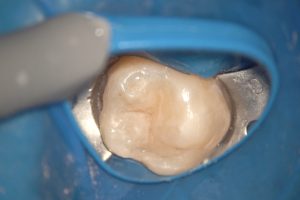

◆ 治療後の状態

治療後は、どの部分を治療したのか分からないほど自然な仕上がりになりました。